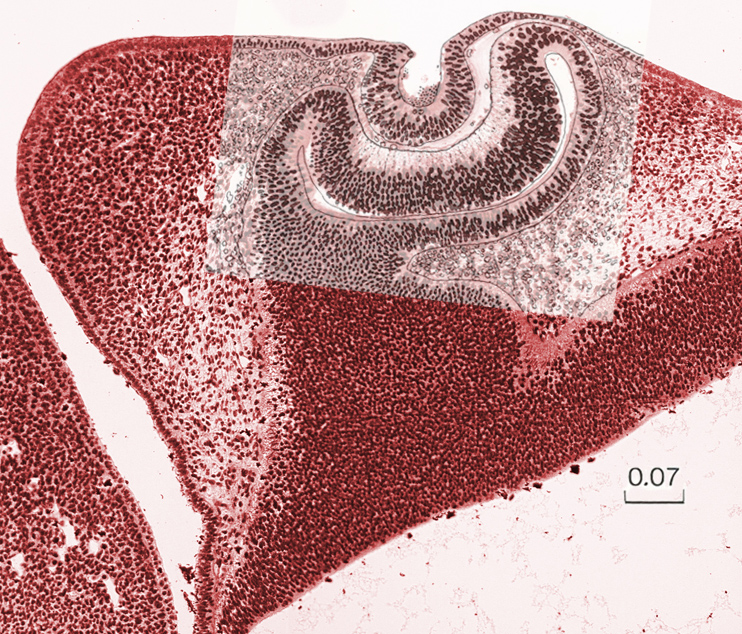

Section through the lens - Overlay

Keywords:

lens

Source:

The Virtual Human Embryo